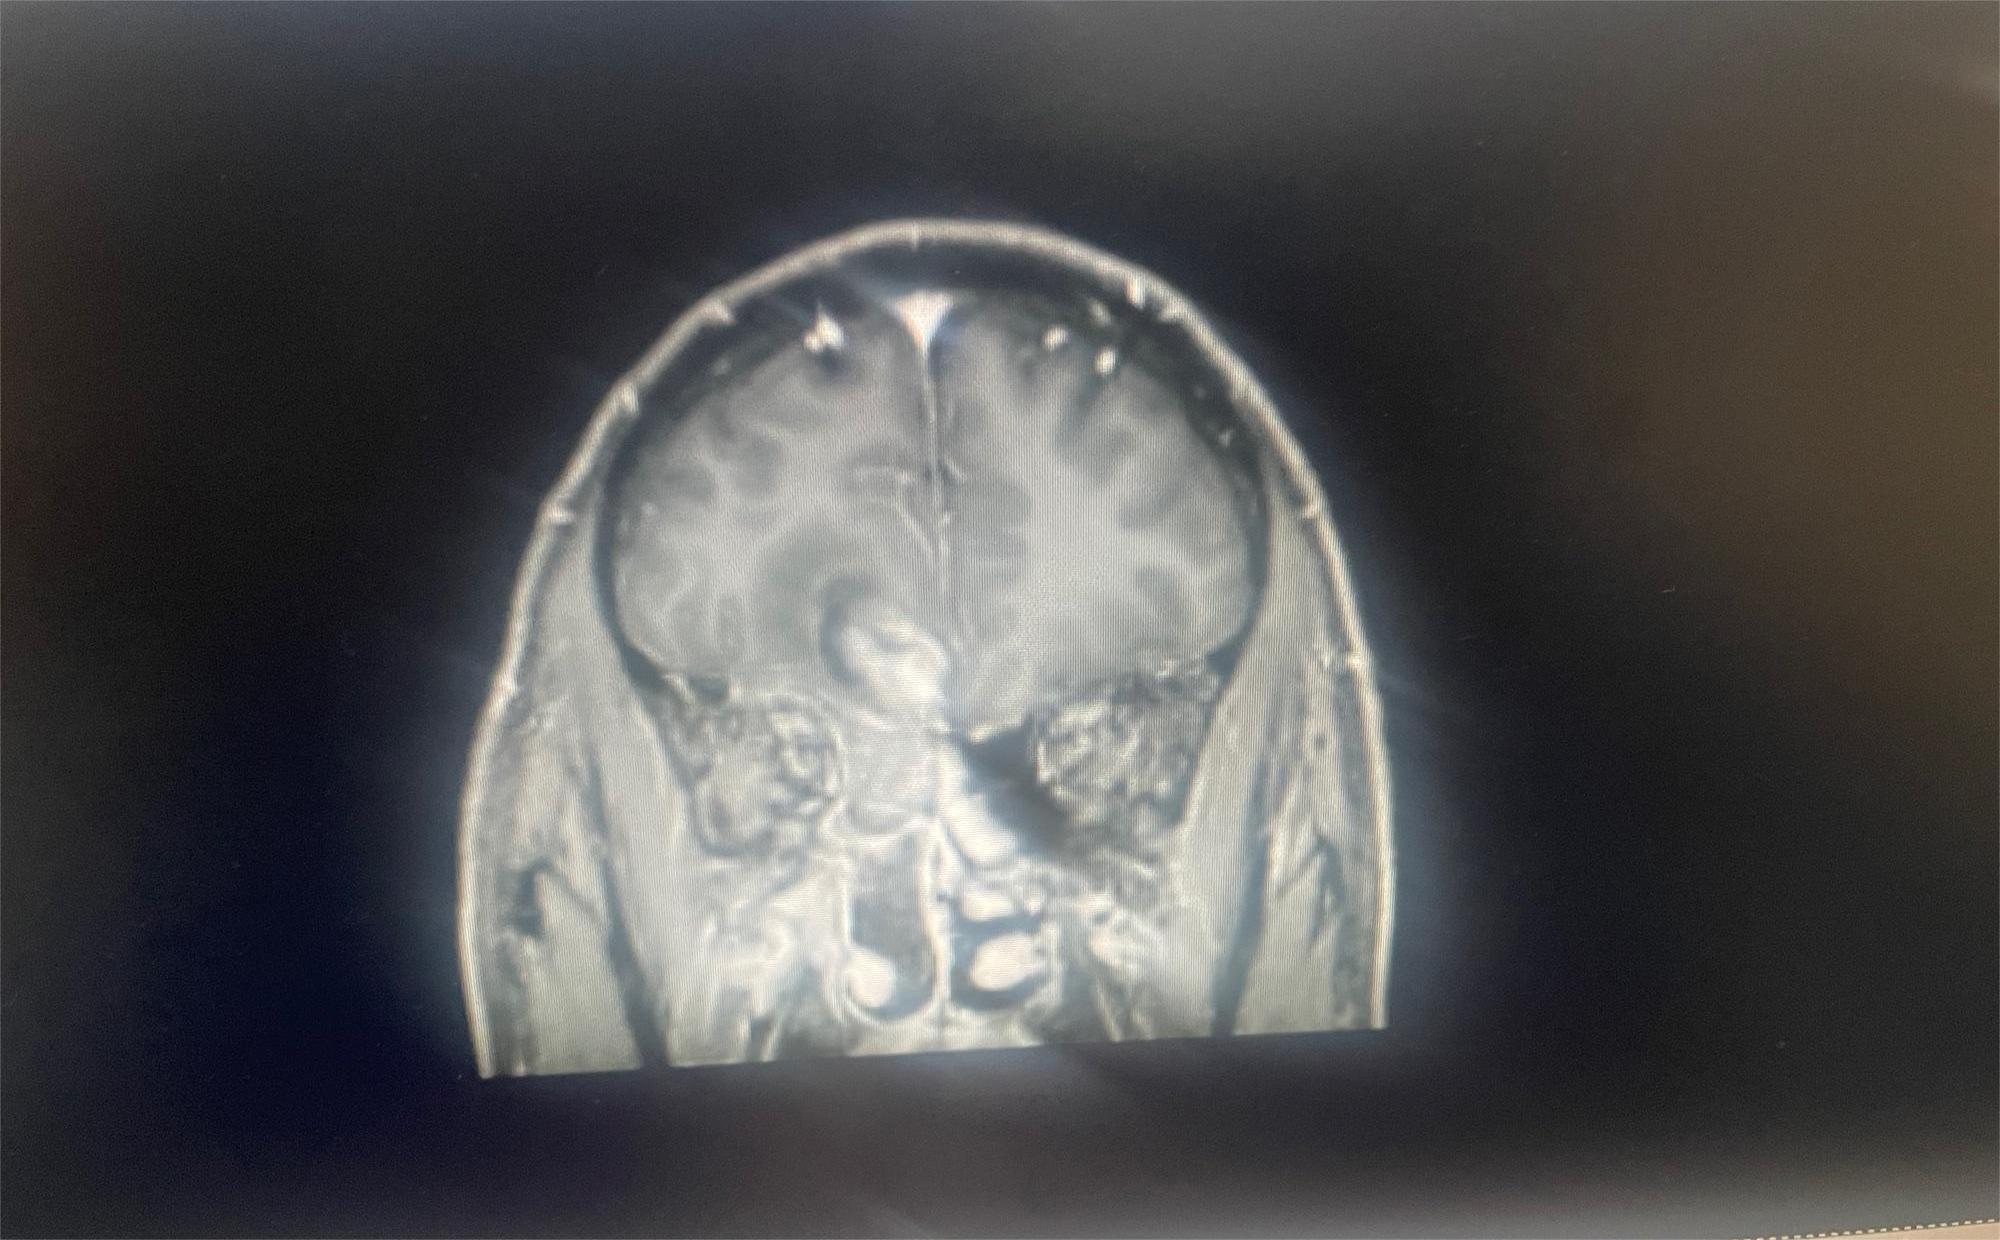

O=O 02023-08-02 患者家属这是我83岁奶奶的报告,哪位朋友能帮忙看看这是到什么阶段了,发展到晚期还有多长时间。 医生说肿瘤挨着血管,做不了手术,年...